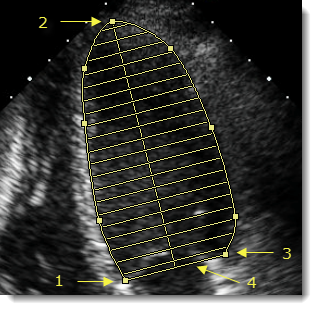

- Κάντε κλικ στο ένα άκρο (1) της βάσης της κοιλότητας για να τοποθετήσετε την πρώτη λαβή του εργαλείου σήμανσης.

- Κάντε κλικ στο περίγραμμα της κοιλότητας στην κατεύθυνση της κορυφής (2) για να τοποθετήσετε επιπλέον λαβές για ακριβή σχεδίαση περιγράμματος της περιοχής του.

- Αφού τοποθετήσετε αρκετές λαβές κατά μήκος του περιγράμματος της κοιλότητας, κάντε διπλό κλικ στο άλλο άκρο της βάσης (3) για να ορίσετε την πρώτη λαβή.

Η γραμμή βάσης (4) ολοκληρώνεται αυτόματα και σχεδιάζεται ο μεγάλος άξονας έως την κορυφή της κοιλότητας. Ο όγκος της κοιλότητας υπολογίζεται με τη μέθοδο των δίσκων, βάσει των 20 δίσκων που οπτικοποιήθηκαν στην εικόνα.

- Για βελτίωση του υπολογισμού, επιλέξτε τη σήμανση και κάντε κλικ στις λαβές του περιγράμματος για να προσαρμόσετε το σχήμα ή σύρετε τη λαβή του μεγάλου άξονα (2) για να μετατοπίσετε την ευθυγράμμιση των δίσκων.